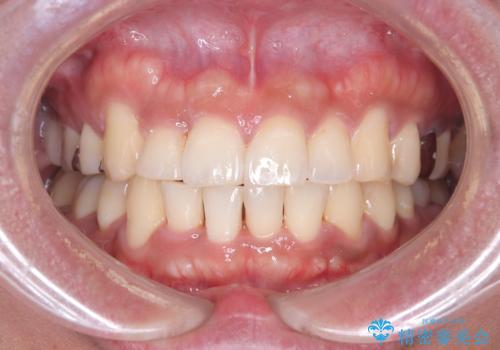

【ワイヤー矯正】八重歯と下の歯の凸凹を治したい

- 主訴:右上の八重歯と、下の歯の凸凹を治したい

上顎右側第一小臼歯と下顎右側第一小臼歯を抜歯しワイヤー矯正を行いました。

右側2級、左側1関係だったため、右側上下第一小臼歯を抜歯し、ワイヤー矯正を行いました。

期間:2年6カ月